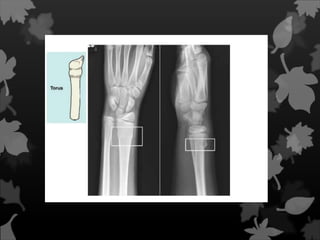

Fratura de Toro

Fratura Incompleta Nesse tipode fratura o osso não é fraturado em duas partes, mais comum em crianças. Também é conhecida como fratura em fissura.

Fratura de Galhoverde Fratura típica que ocorre na criança, onde há extrema elasticidade do osso. Um dos córtices quebra e o outro fica “amassado”.